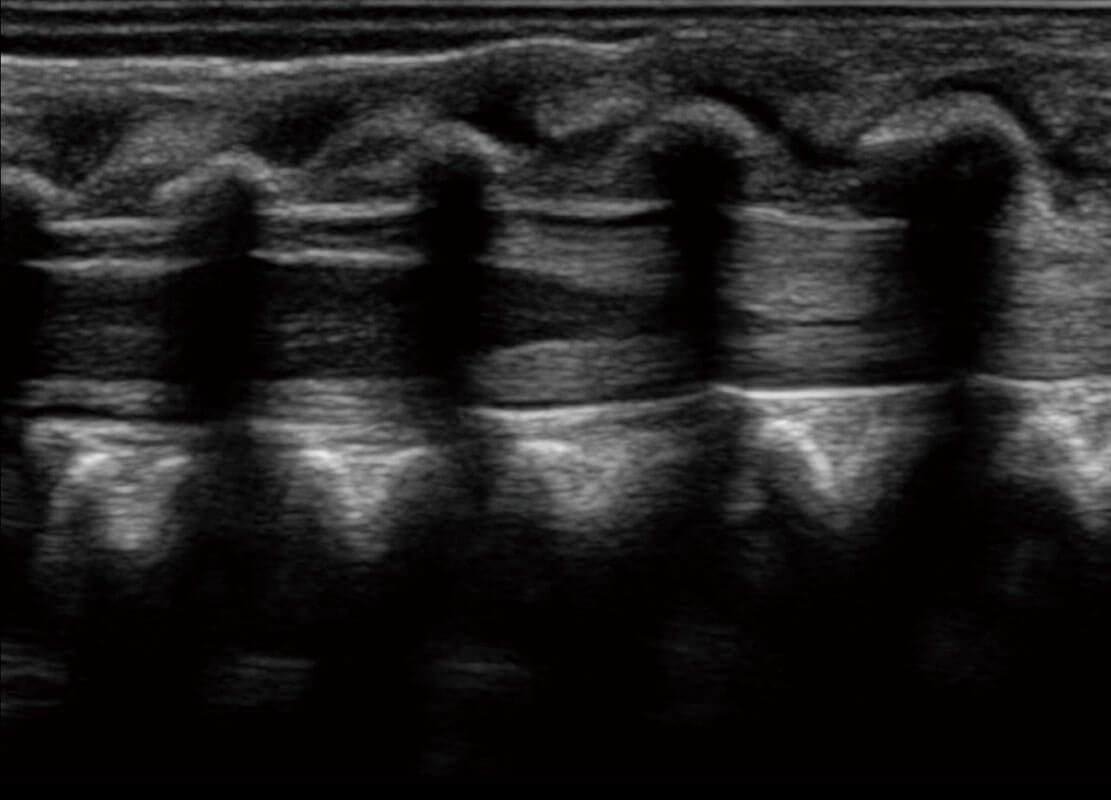

P60搭載寬頻帶線陣探頭、寬景成像、彈性成像技術(shù),為您提供乳腺應(yīng)用方案。P60支持高頻相控陣探頭、線陣探頭、腹部高頻探頭、腹部微凸探頭等,豐富的探頭群搭載敏感的彩色血流成像,適用于新生兒多種臟器檢測要求,滿足新生兒篩查需求。

新生兒脊髓圓錐